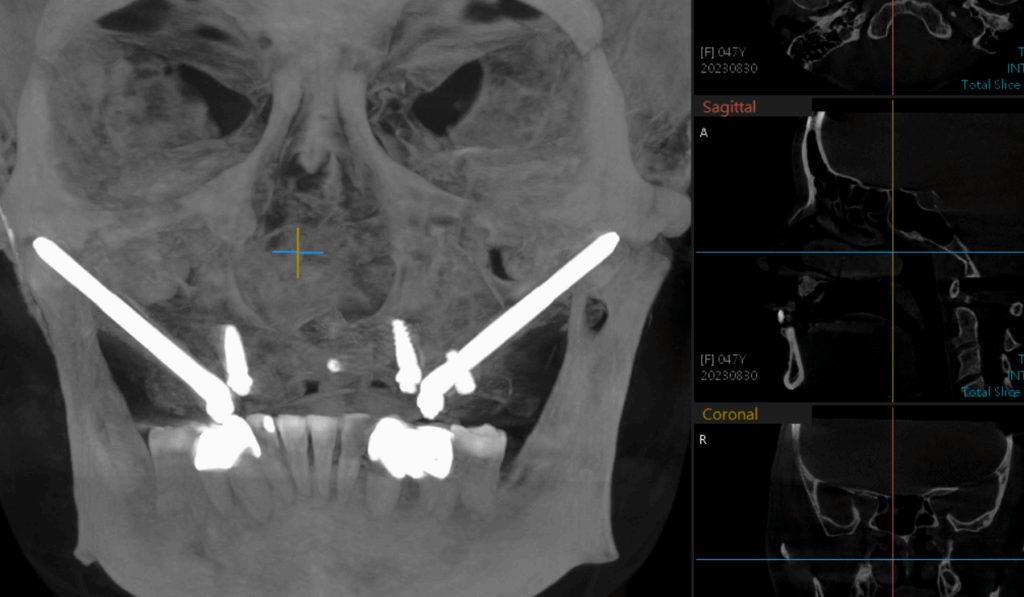

五、顴骨植牙(Zygoma Implant)

技術原理

當上顎骨流失嚴重,利用顴骨(顴弓)打入特殊長型植體。